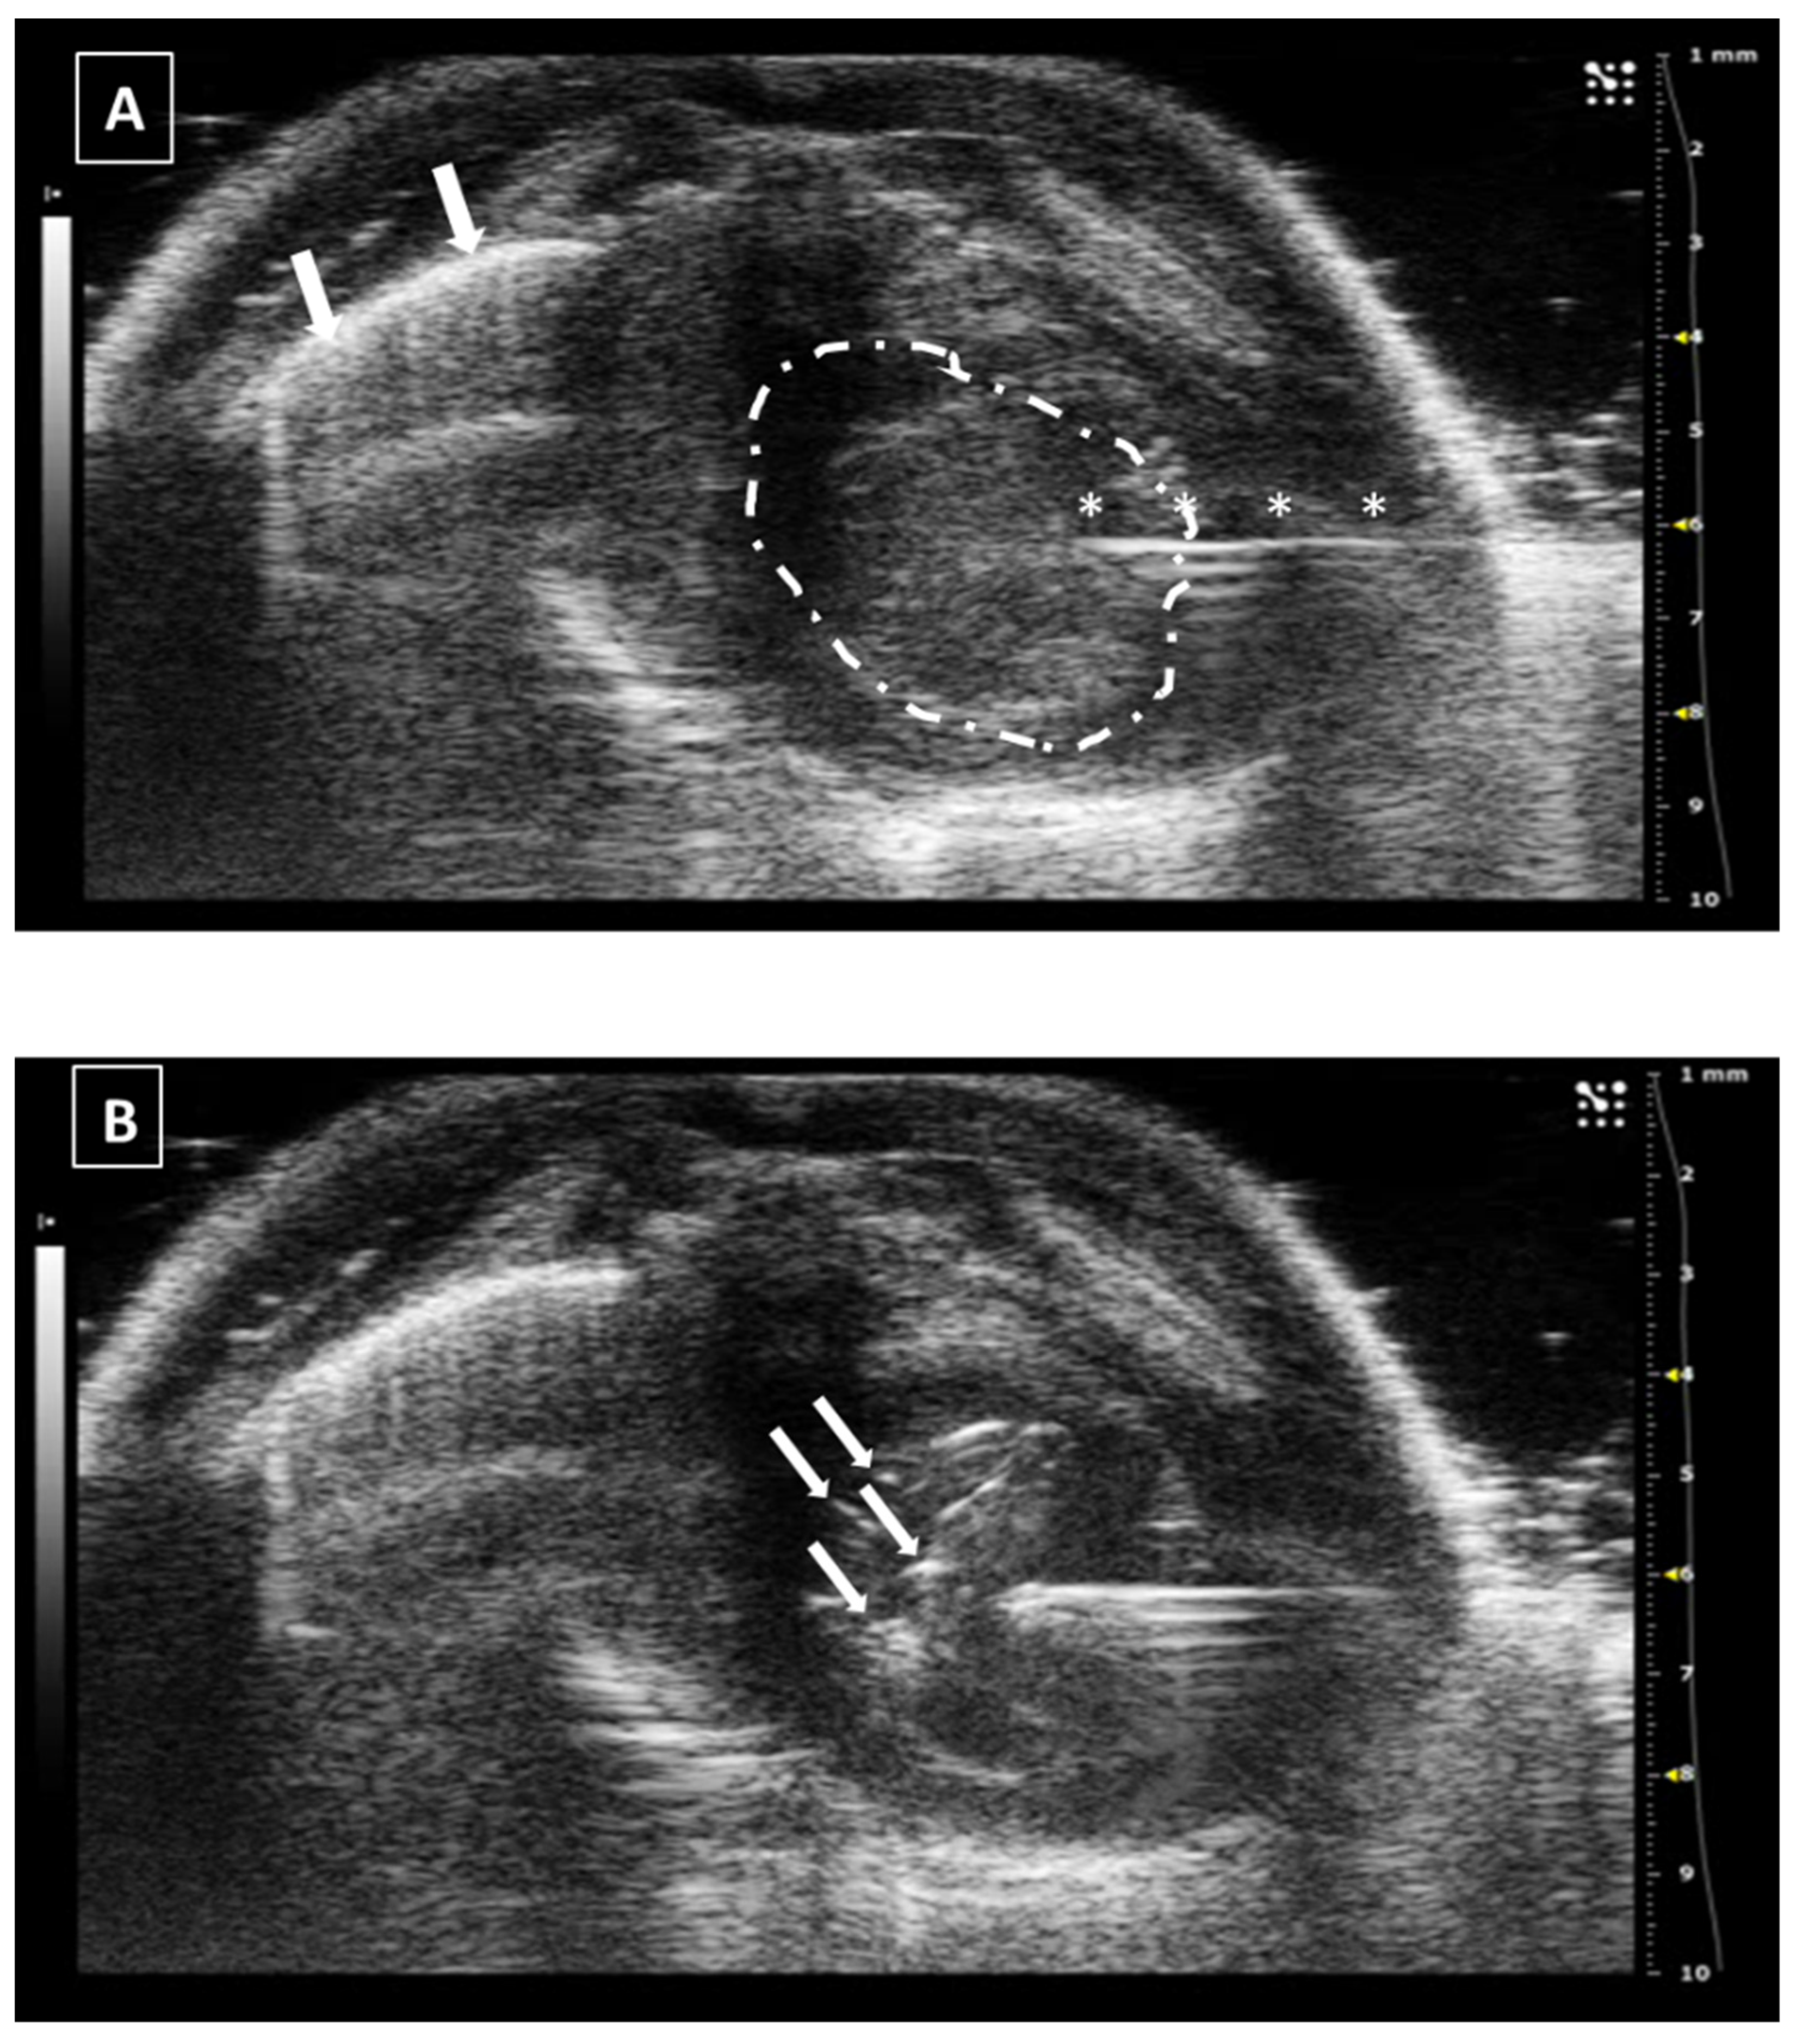

The needle can be seen inside the left ventricle as a hyperechoic linear structure with reverberation artifacts in an anechoic background. During the injection, we will be able to see some small hyperechoic dots coming from the needle. These are microbubbles created during the needle filling. These dots will confirm the correct injection in the anechoic ventricular cavity. Once the injection is completed, the needle can be removed. An example of an intracardiac injection can be seen in Figure 3.

The duration of this process depends on the expertise of the user. An experienced ultrasonographer can do the injection in less than a minute. The major risk of this procedure is the incorrect injection in the right ventricle, the lung, or the mediastinum. We will not see the hyperechoic bubbles arising inside the left ventricle. Other less frequent errors can be damaging the aorta the cava vein or any of the cardiac atriums. In these cases, we will see an acute intrathoracic hemorrhage.

Figure 3. Intracardiac injection. (A) Preinjection image. Needle is marked with white asterisks and left ventricle area is surrounded by a dashed line. Lung artifact is labeled with white arrows. (B) Injection moment. Multiple white dots (marked with white arrows) inside the left ventricle correspond to microbubbles injected with the suspension. Images obtained with 40 MHz frequency.